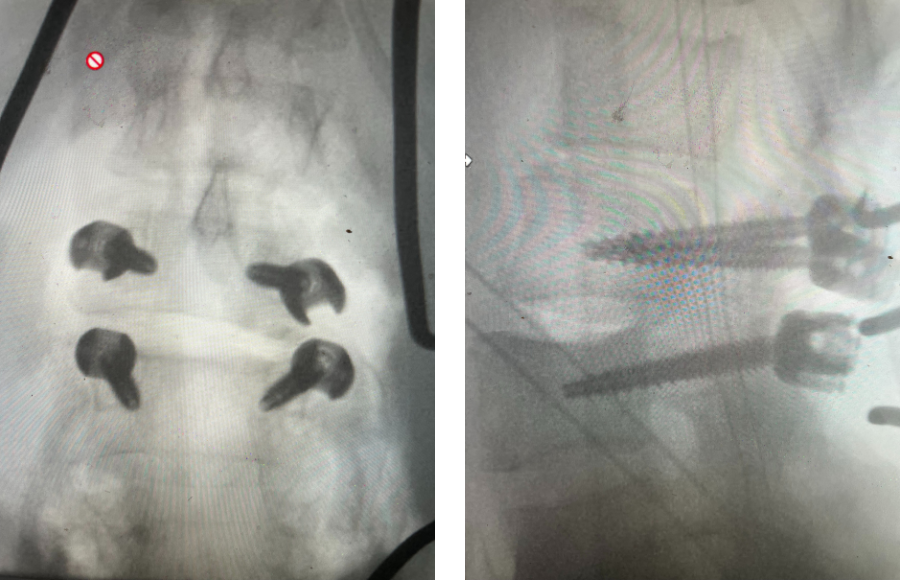

Fig 1: Plain X-rays demonstrating a grade 1 L45 spondylolisthesis with dynamic translation of approximately 4 mm (arrow).

Plain lumbar x-rays were done with flexion/extension views. Surprisingly the patient had 4 mm of anterior translation and slight angulation in flexion (Fig 1). This was unexpected because in degenerative spondylolisthesis the patient more commonly has auto stabilized by formation of stabilizing arthritic structures and has no motion on dynamic x-rays. However, approximately 20% of patients will have some degree of translation on flexion-extension x-rays with degenerative L4-5 spondylolisthesis. Because she had failed all means of conservative management, it was felt that the patient would benefit by a lumbar decompression and instrumented fusion because of the acute instability demonstrated on x-rays and her age.

Revision surgery is more involved than primary surgery. In order to start decompressing this large complex, you must develop a plane; you have to find the edge of sometimes a remnant of a lamina or the lamina that can be buried in scar. You must carefully dissect the edge with a sharp upbiting curette and then either using a sharp Leksell to start removing this lamina or use a fine Kerrison to widen the plane and exposure and begin to expose the normal ligamentum above. In this case it was critical to expose and decompress the L3 nerve roots bilaterally. What is quite helpful is finding the inferior edge of the L2 facets. Then one must lift up the inferior L2 process up with a curette and simultaneously insert a Kerrison into joint space and remove the whole facet process. This is a great move because it allows access to the plane between the superior facet and the descending nerve root and a starting point to fully decompress the nerve root. Because of scarring there often is not a clear plane in order to accomplish the decompression. Care is taken to make sure there is a clear separation between edge of bone and dura during the process of inserting a Kerrison edge. The important part of this is feeling your opening and actually using your Kerrison as a dissecting tool once an edge has been established to perform a foraminotomy. We were able to remove the inferior L2 facet process with impunity as we knew we were performing an instrumented fusion to L2. The patient’s had a prior L3-5 instrumented fusion which upon exploration was solidly fused. It was decided to remove her prior hardware as it served its purpose and add a short segment from L2-3 (Fig 5). Patient did well after her surgery with relief of her right leg pain.

Fig 5: intraoperative fluoroscopic images demonstrating L2-3 screw placement.